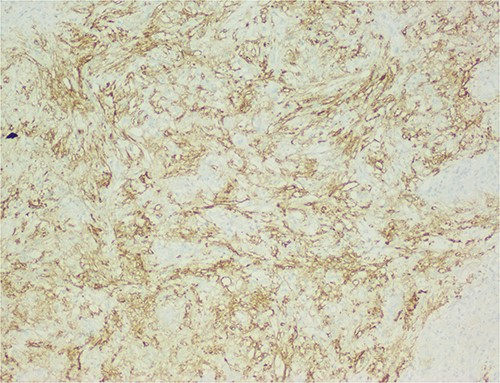

The histological evaluation of the surgical specimen revealed a storiform fusiform cell neoplasm with expansive borders, areas of a myopericytomatous pattern, and the presence of rhabdoid cells (Fig. 4). The neoplastic cells, spindled to oval, with eosinophilic and granular cytoplasm and with mild nuclear atypia, were organized in small bundles (Fig. 5). Anomalous arterial structures were observed. Neither necrosis nor mitotic figures were identified. The immunohistochemical study revealed immunoreactivity of neoplastic cells for SMA, HHF35 (Fig. 6) and HMB45 (Fig. 7), Calponin, S100 and CD31. The margins did not intersect the neoplasm. Thus, contrary to the preoperative diagnosis of hepatocellular carcinoma, the morphological aspects and the immunohistochemical profile favored the diagnosis of epithelioid angiomyolipoma.

Liver parenchyma partially occupied by a neoplastic proliferation with expansive borders.

The neoplastic cells are organized in small bundles. The cells are spindled to oval, with eosinophilic and granular cytoplasm and with mild nuclear atypia.